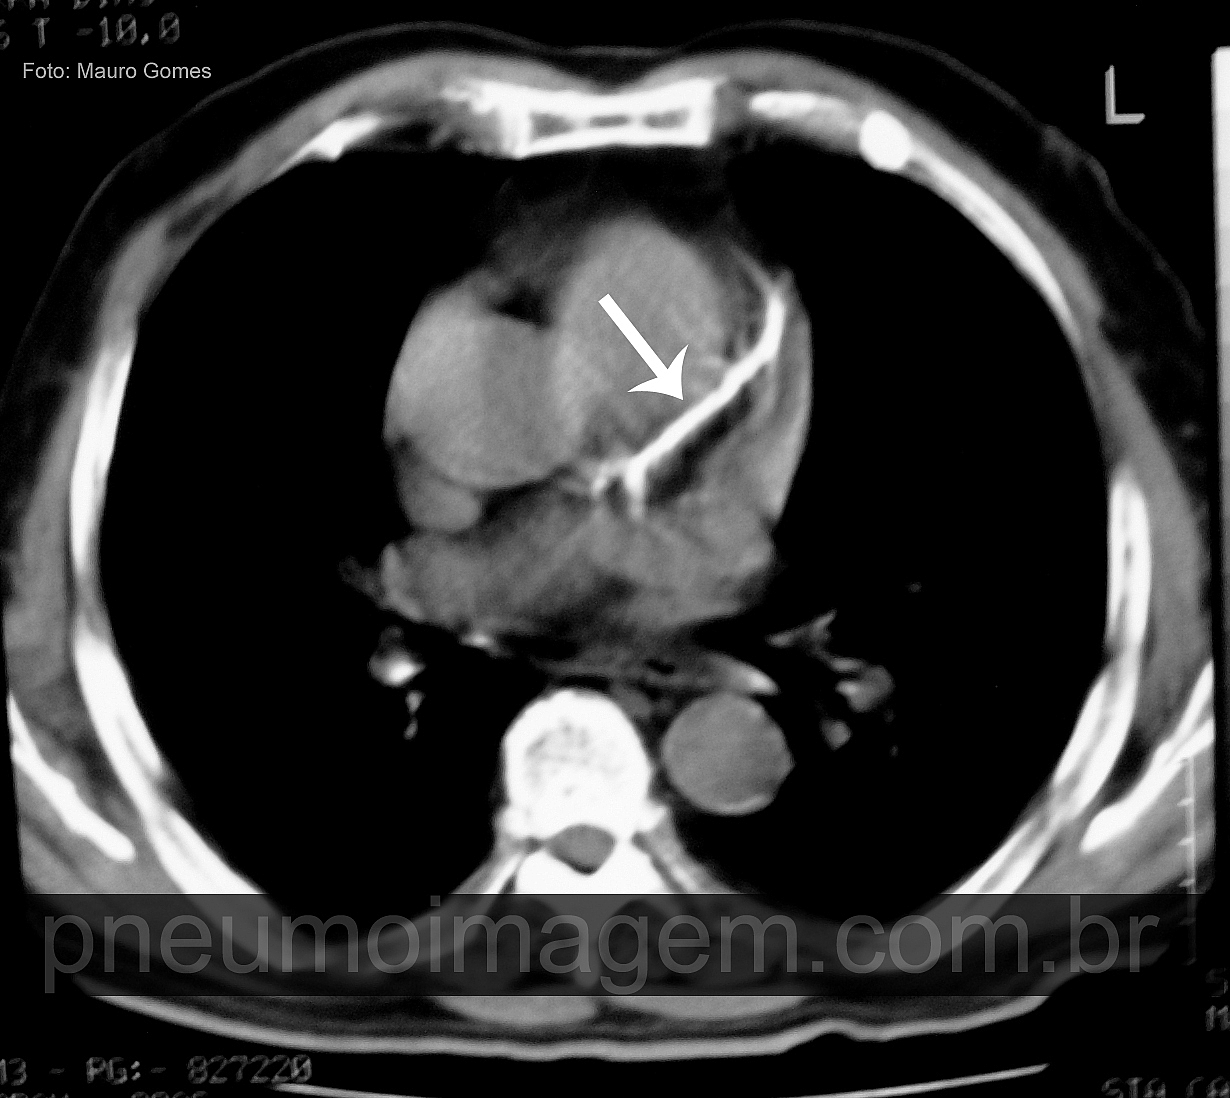

CASO CLÍNICO #25

CASO CLÍNICO #25O que é essa imagem e o que ela significa? Deixe seus comentários abaixo.

What is this image and what it means? Write your comments below.